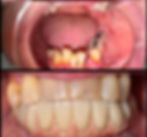

Upper All On 4

Full arch metal ceramic (Zirconia & Titanium)